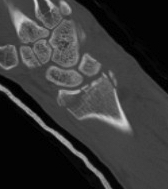

CT

Radial styloid + dorsal rim fractures